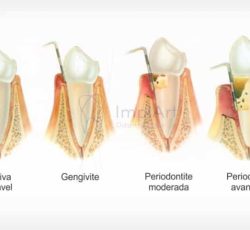

A periodontite aparece com o acumulo da placa bacteriana nos dentes, ela produz toxinas que incomodam a gengiva, gerando uma inflamação.

E essa inflamação, se não for tratada, pode evoluir para uma gengivite. E a evolução da gengivite é justamente a periodontite.

Ou seja, a inflamação se dissemina para o osso e tecidos de suporte dos dentes, deixando-os moles a ponto de precisarem ser extraídos.